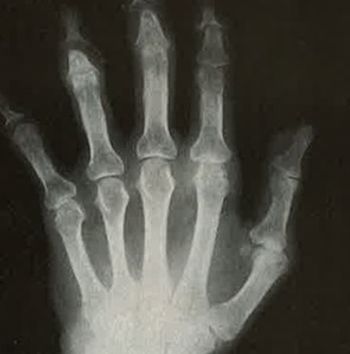

A 56-year-old woman presents with persistent pain and tenderness in both hands. A workup reveals she has erosive osteoarthritis. Which factors are most strongly associated with increased pain?